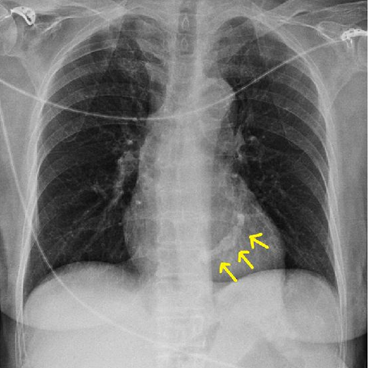

consists of the left lateral border of the left ventricle

right heart contour

is the right lateral border of the Right Atrium (RA)

density; adjacent lung

If the heart contours are not clearly seen, this may indicate increase in ___ of the ___.

middle mediastinum

The heart is located in the ___

Aortic Knuckle

represents the left lateral edge of the aorta as it arches backwards over the left main bronchus.

Mediastinal Contours

Displacement or loss of definition of these contours can indicate diseases such as aortic aneurysm or adjacent lunch consolidation

descending thoracic aorta

The contour of the ____ can be seen in continuation from the aortic knuckle.